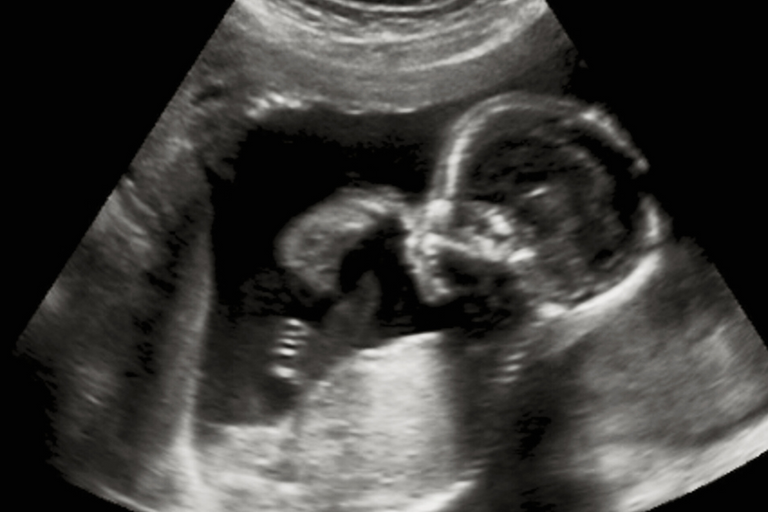

With Mira, Nichole W was able to identify and pinpoint when she was ovulating. The useful information helped the couple to get pregnant. At the time of writing, Nichole W is eight and a half weeks in. Thrilled to have found Mira on her pregnancy journey, Nichole W told everyone she knew about Mira. She even passed down her kit to a close friend who has similar disabilities and is trying to get pregnant.